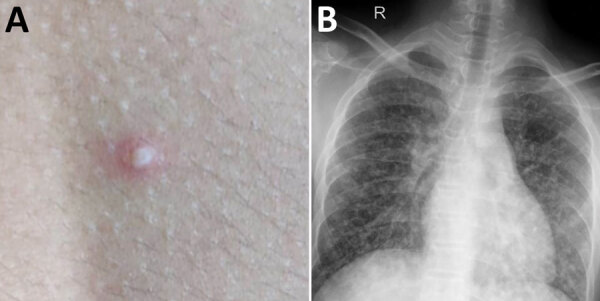

Description:In 2019, Burkholderia pseudomallei was isolated from the backyard of 2 siblings with melioidosis in Kerala, India. This finding highlights the value of healthcare providers being aware of risk for melioidosis in febrile patients, of residents taking precautions when outside, and of increasing environmental surveillance for B. pseudomallei in this region.